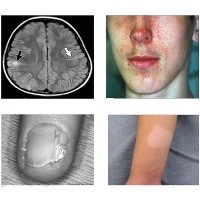

1. Pasien dengan tumor di otak (Foto 1) biasanya menunjukkan tanda-tanda epilepsi dan atau retardasi menta.

2. Pasien dengan tumor di kulit wajah (Foto 2 - disebut dengan facial angiofibroma) menunjukkan tanda-tanda seperti jerawat yang parah.

3. Sementara banyak pasien dengan hanya tumor jaringan ikat pada lipatan kuku tidak menunjukkan gejala apapun selain hanya lesi kecil pada salah satu sisi kuku (Foto 3 - disebut periungual fibroma).

4. Banyak pula dari pasien yang hanya menunjukkan tanda putih seperti panu dengan ukuran besar di beberapa bagian tubuhnya (Foto 4 - disebut hypomelanotic macules).